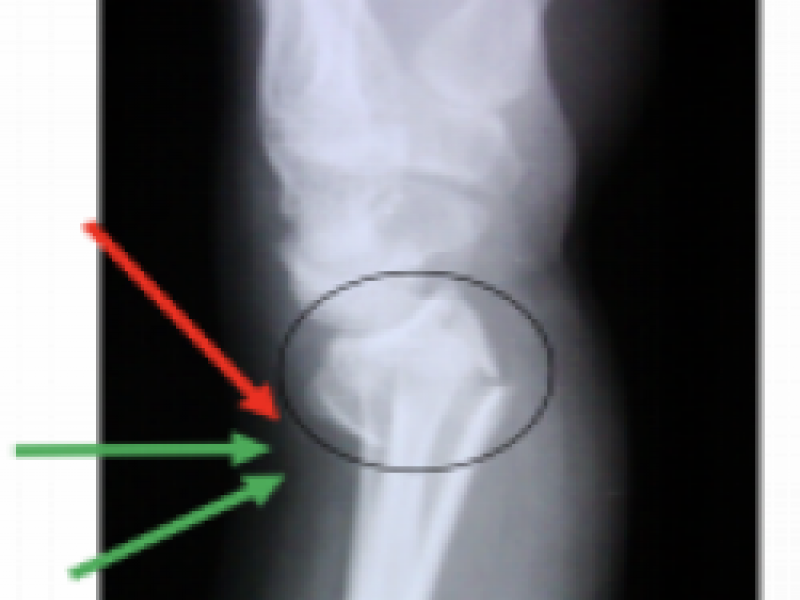

Board Review: Oh SNAP!

August 08 2020

A 21 year old otherwise healthy female presents to the ED

August 01 2020

19-year-old male with past medical history significant for